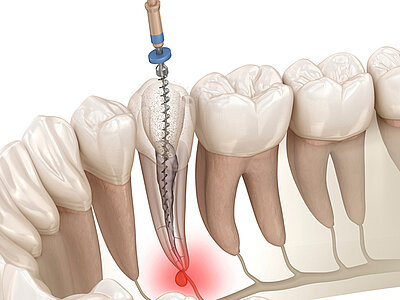

wurzelspitzenresektion

Ein minimal-invasiver Eingriff, bei dem die entzündete oder infizierte

Wurzelspitze eines Zahns entfernt wird